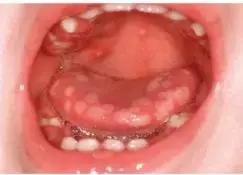

疱疹性咽峡炎患者的口腔疱疹和溃疡一般常位于腭舌弓、软腭、扁桃体和悬雍垂,疱疹数量通常不超过10个。少见情况下,疱疹也可见于硬腭、舌或颊黏膜。(如下图)▼